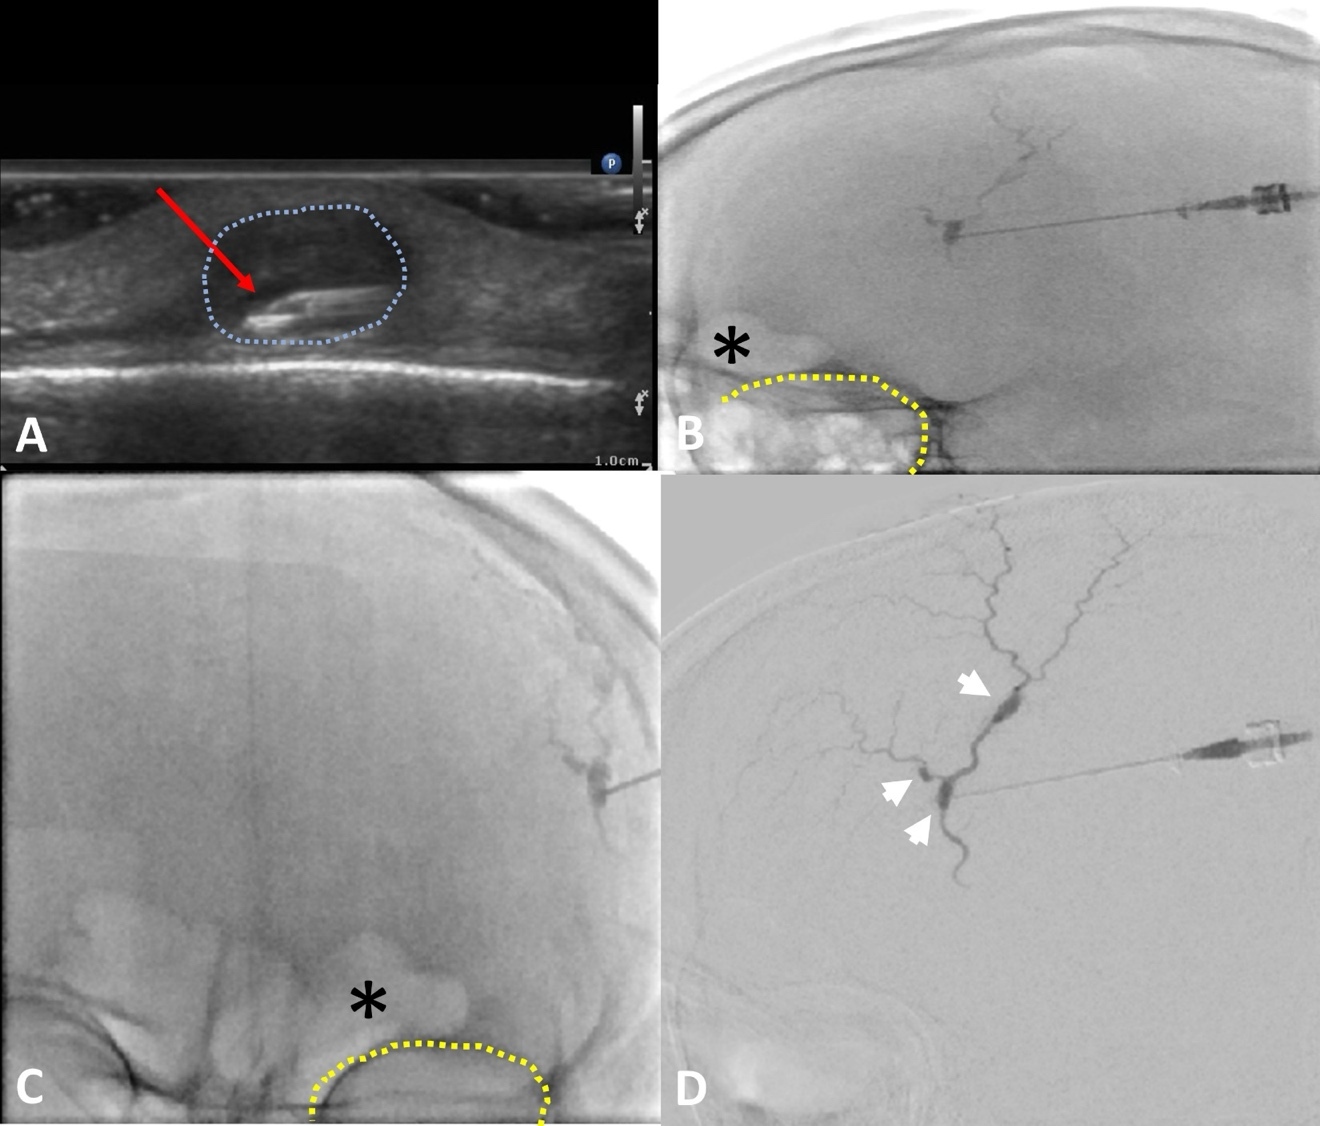

After discussion and counseling regarding the treatment options, the patient elected to have the percutaneous procedure performed in lieu of surgery as his initial choice of treatment. The patient emphasized understanding that a surgical excision may be required in the future for complete cosmetic and symptomatic resolution. Two weeks after the ultrasound study was conducted, the pseudoaneurysms were treated with direct, percutaneous pseudoaneurysm needle access and subsequent angiogram and n-BCA glue embolization. Specific procedure details include: the procedure was performed under moderate sedation with IV administration of midazolam and fentanyl. The forehead was prepped and draped in sterile fashion and subcutaneous injection of 1% lidocaine was used for local anesthesia. Then, the pseudoaneurysm was percutaneously accessed with a 21-gauge needle under direct US guidance. Angiography through the needle demonstrated successful access to the pseudoaneurysm; which was located at a branch point of the STA. Further angiographic opacification of the vascular territory demonstrated two additional small pseuaneurysms, one arising from each branch (Figure 3).

There was normal venous drainage on the scalp and no evidence of intracranial communication. Embolization with n-BCA glue was then delivered under fluoroscopic guidance. The glue embolized all three pseudoaneurysms including a short segment of the parent inflow artery and short segments of the outflow arteries. The glue cast was well visualized on fluoroscopy. Post-intervention ultrasound confirmed thrombosis of the pseudoaneurysms (Figure 4). The patient tolerated the procedure well without complications.